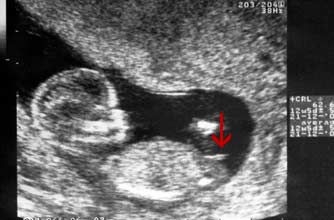

Girl nub: The nub isn't pointing up more than 30 degrees - in fact it's almost horizontal!

小肿块没有指向三十度以上 - 事实上它几乎是水平的!

Boy nub: The nub is at a much steeper angle upwards, indicating that this baby is a boy.

小肿块以一个陡峭的角度向上指,显示这个胎儿是个男孩。